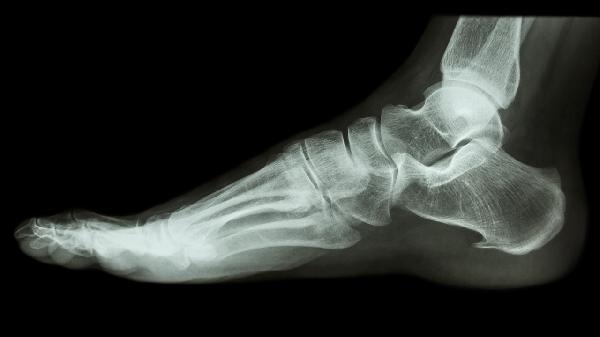

跟骨粉碎性骨折術(shù)后一個(gè)月怎么鍛煉

跟骨粉碎性骨折術(shù)后一個(gè)月可通過(guò)踝泵運(yùn)動(dòng)、直腿抬高訓(xùn)練、膝關(guān)節(jié)屈伸練習(xí)、足趾抓握訓(xùn)練、漸進(jìn)性負(fù)重行走等方式進(jìn)行康復(fù)鍛煉??祻?fù)訓(xùn)練需根據(jù)骨折愈合程度分階段調(diào)整。

在醫(yī)生允許后從部分負(fù)重開始過(guò)渡,初期使用拐杖分擔(dān)體重。每周增加10%-15%負(fù)重比例,6-8周后逐步過(guò)渡到完全負(fù)重。需定期復(fù)查X線確認(rèn)骨折愈合進(jìn)度。